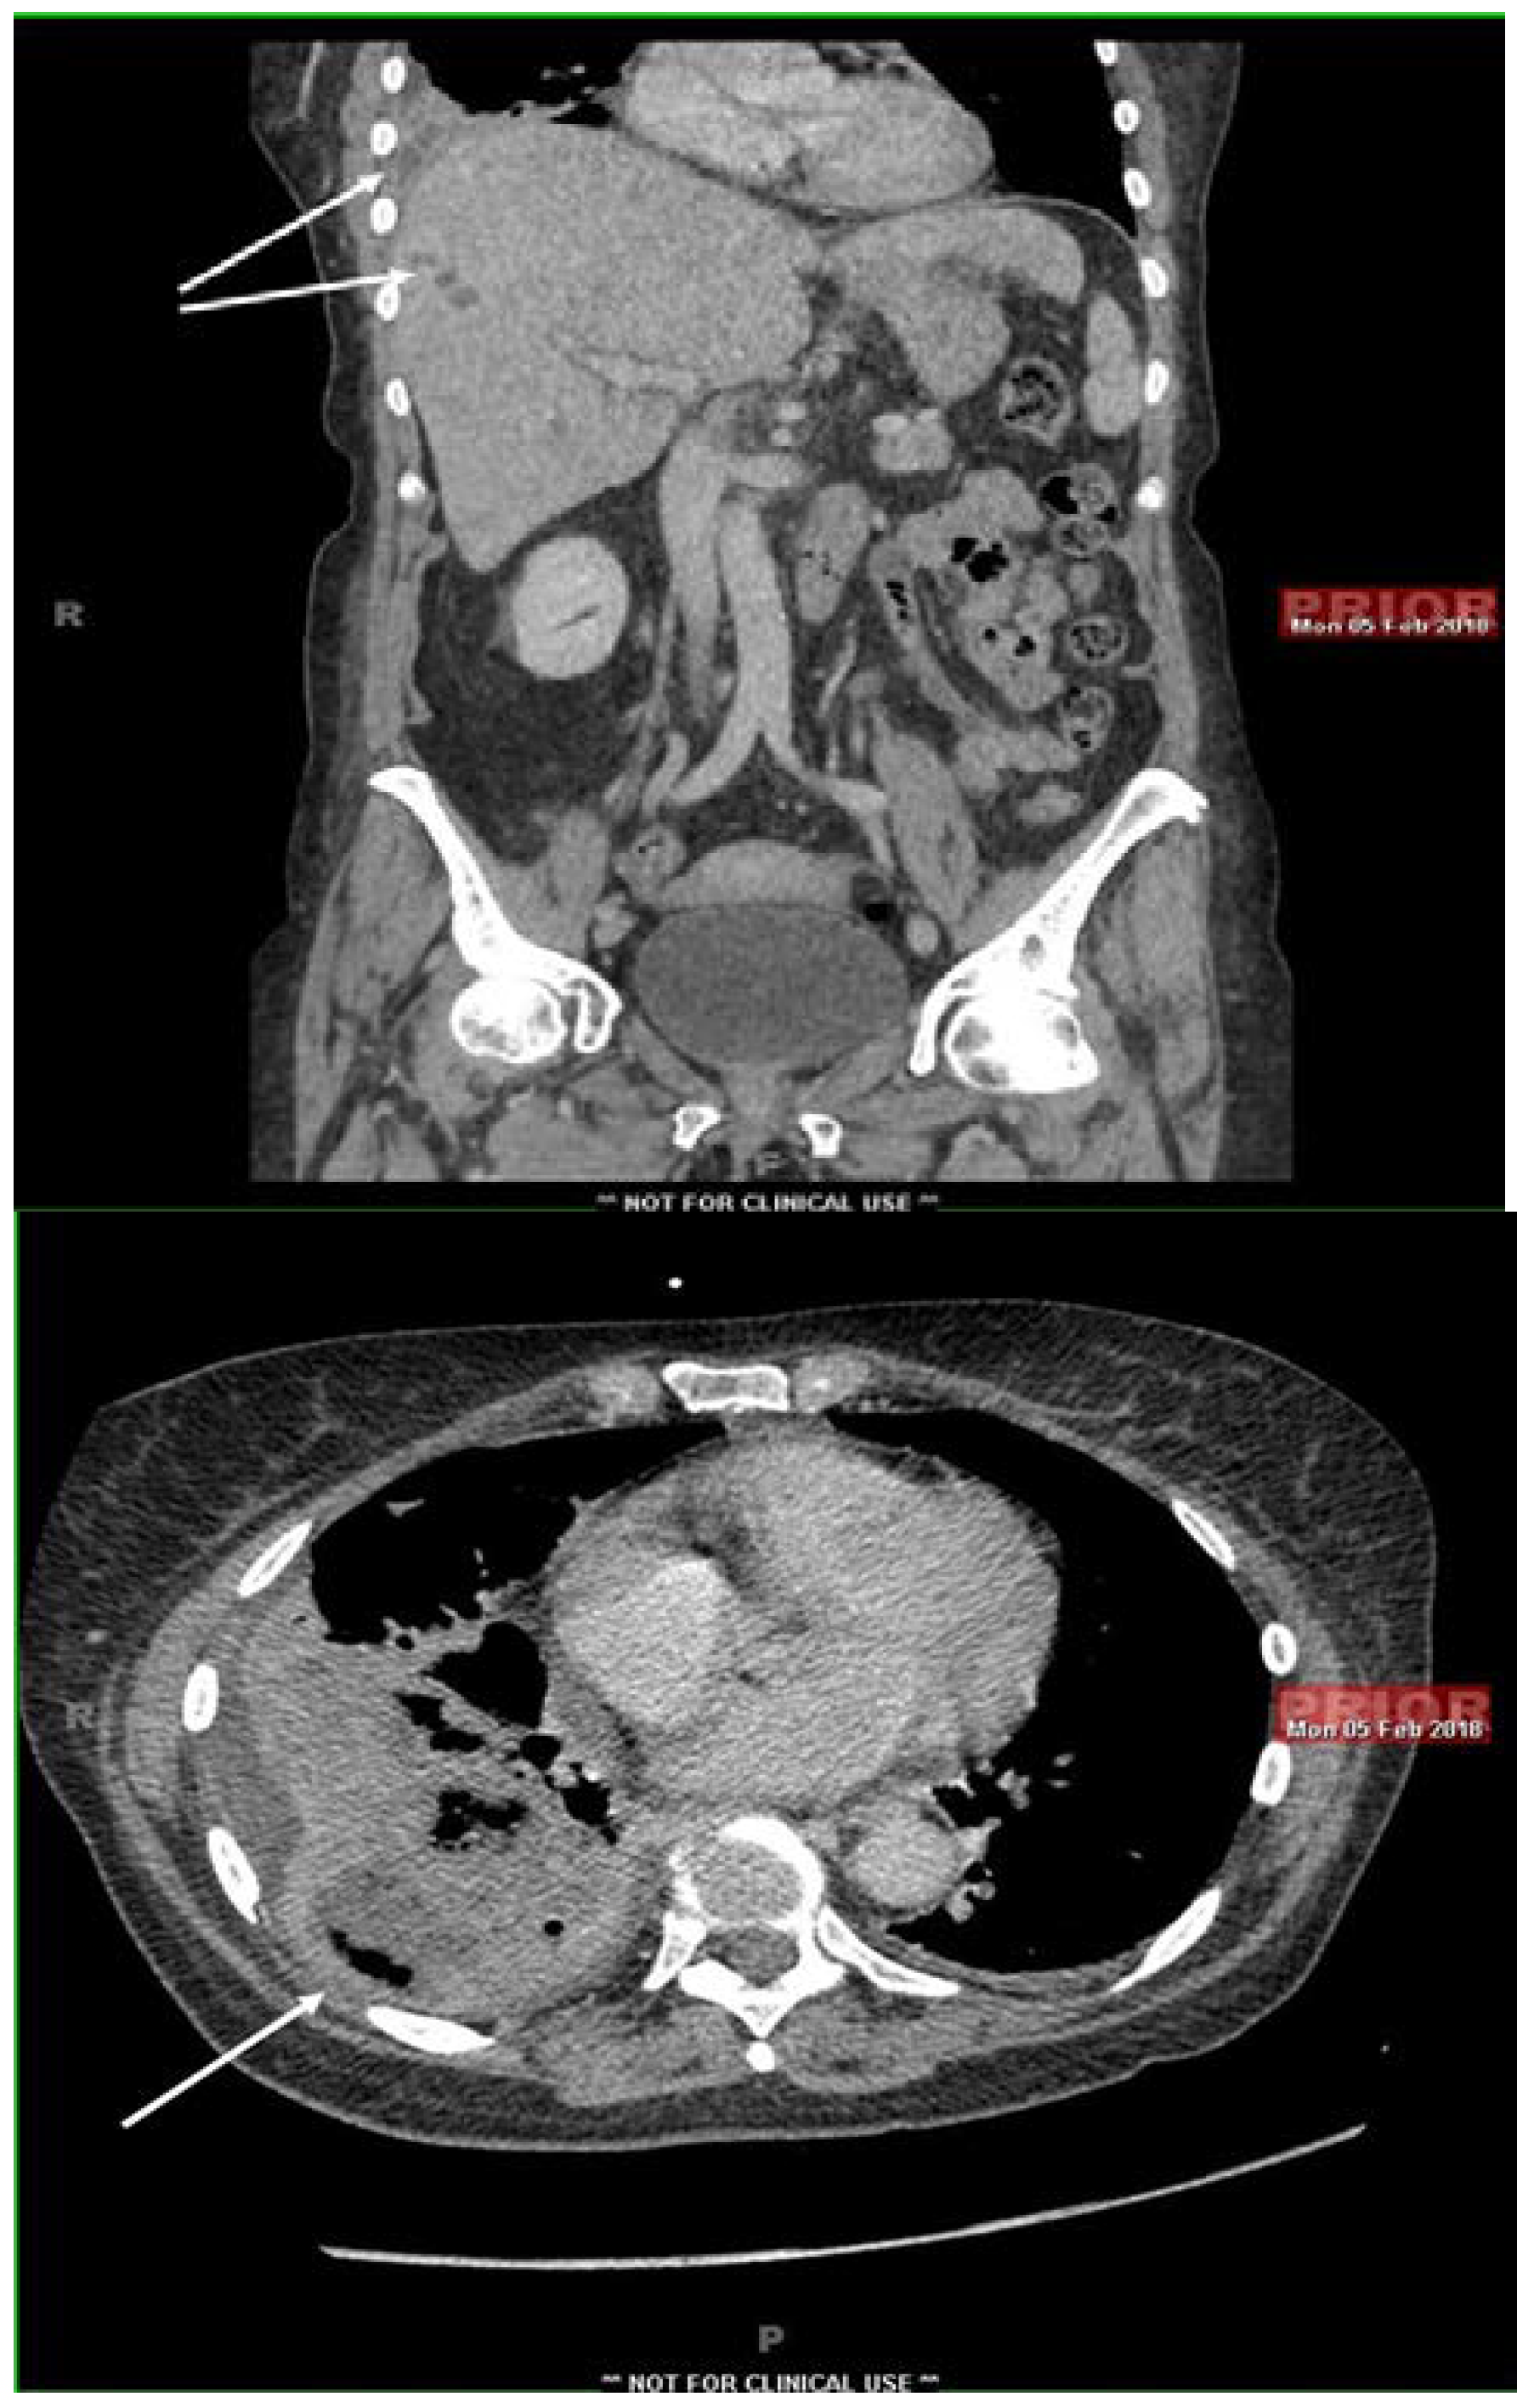

Fusobacterium nucleatum: A Cause of Subacute Liver Abscesses with Extensive Fibrosis Crossing the Diaphragm, Mimicking Actinomycosis

Case report